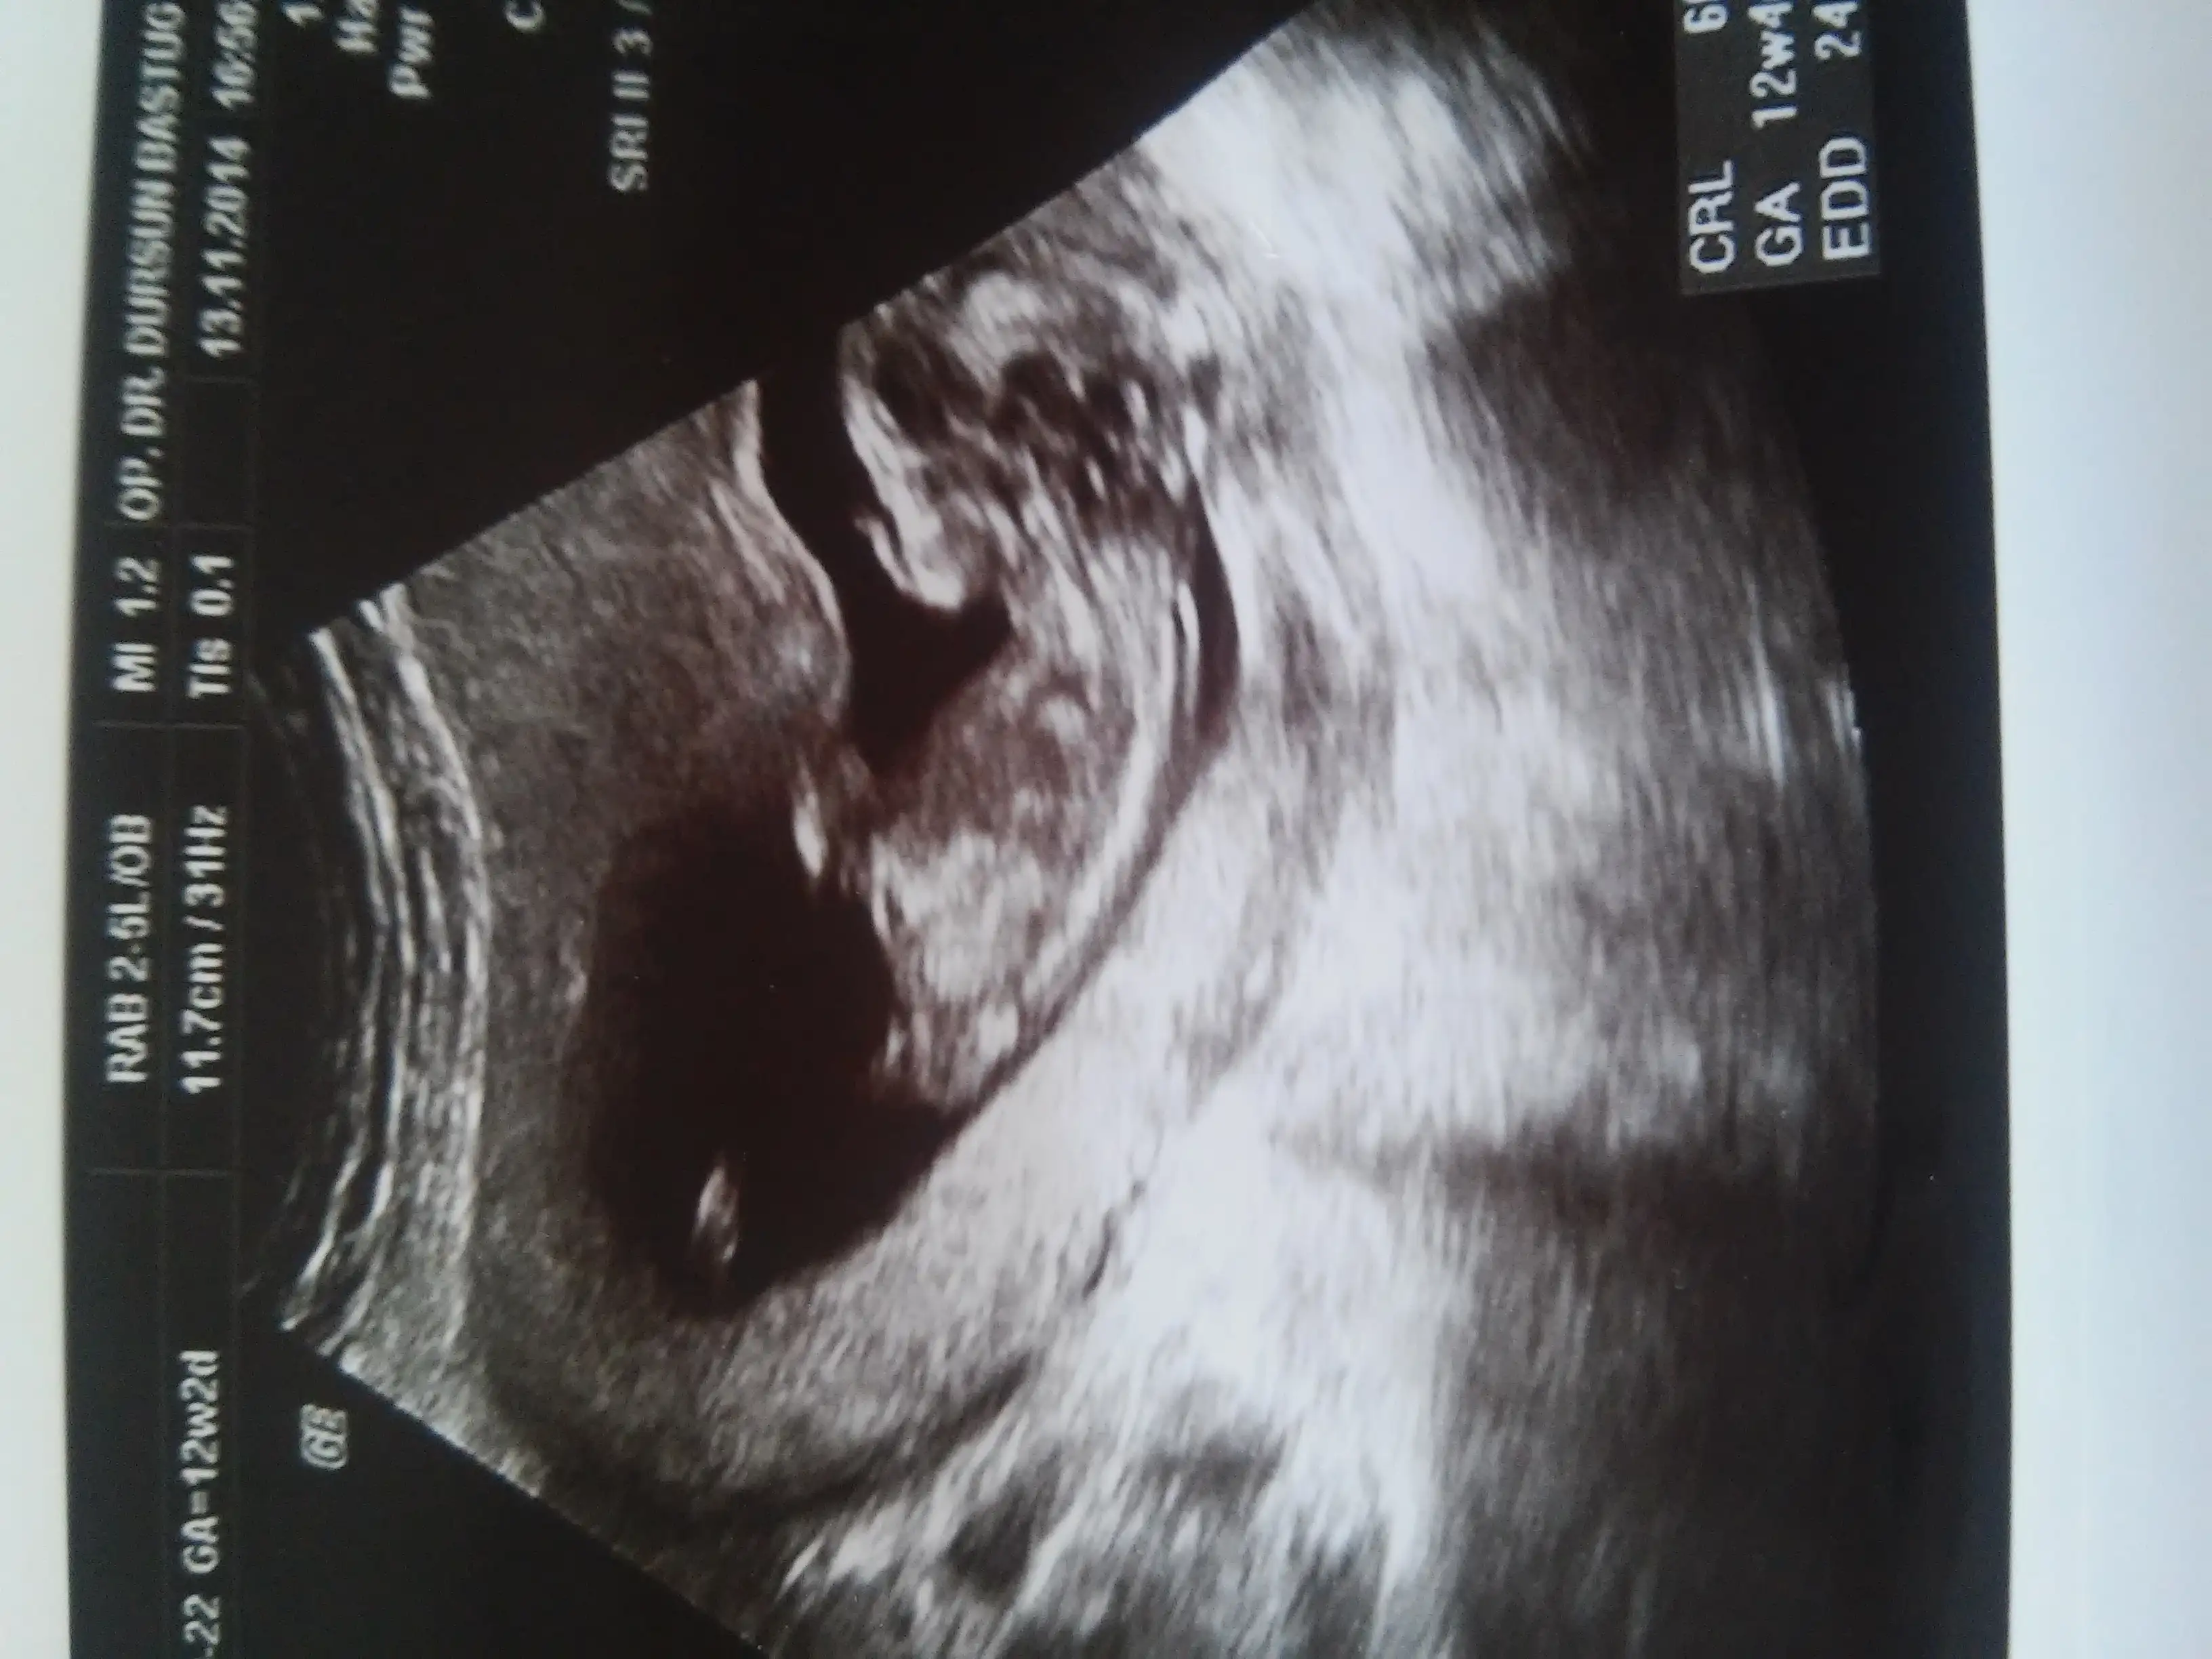

Kızlar benimkinide tahmin edin lutfen cok merak ediyorum 13 haftalığım

Zeyyal ve mavi ikinizinkinide kiza benzettim öğrenince haber verin

Net gorebiliyo musun ? Haftaya gittigimde cekilen fotoyu da atiyim mi canim ?kiz goruyorum hep ruyamda. Genelde ters cikar ruyalarim ama bu kez duz cikti sanirim. Allahim saglikla dogmasini nasip etsin

Net diyemem canm haftaniz 13 ve paralel gordugum bisi var egr o nub ise ve hala paralel duryo oyuzdem kiz olabilivegini düşündüm kesin haber ver tamammi merak ettim bakalim dogrumu gormusum gordgum nubumuymus anlamis olurum